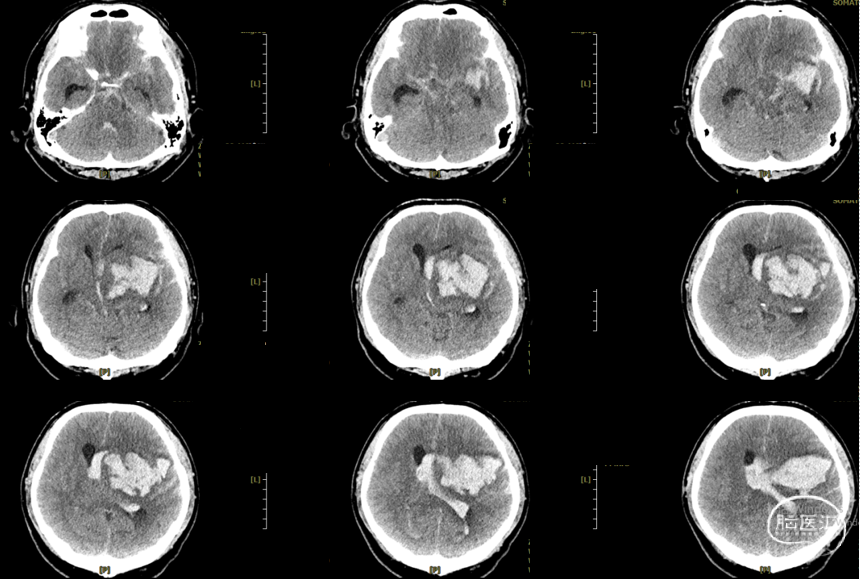

辅助检查:头胸部CT平扫2026-03-14我院脑出血并破入脑室,请结合临床复查,蛛网膜下腔出血。双肺少许纤维灶,双肺坠积性改变,请结合临床隔期复查,双肺少许小结节,考虑低危结节可能,建议结合临床年度随诊复查双肺部分小叶间隔增厚,肺水肿不除外,建议结合临床短期复查,冠脉壁钙化灶,胆囊结石。头颈部CTA2026-03-14我院颅内动脉轻度粥样硬化性改变,左侧优势型椎动脉,椎基底动脉迂曲延长。

初步诊断:1. 左侧额、岛叶、基底节脑出血破入脑室动静脉畸形?2. 脑疝;3. 高血压病3级(极高危)?4. 肺炎;5. 肺结节;6. 胆囊结石;7. 肺水肿;8. 脑动脉粥样硬化。

2026.3.14术后即刻: